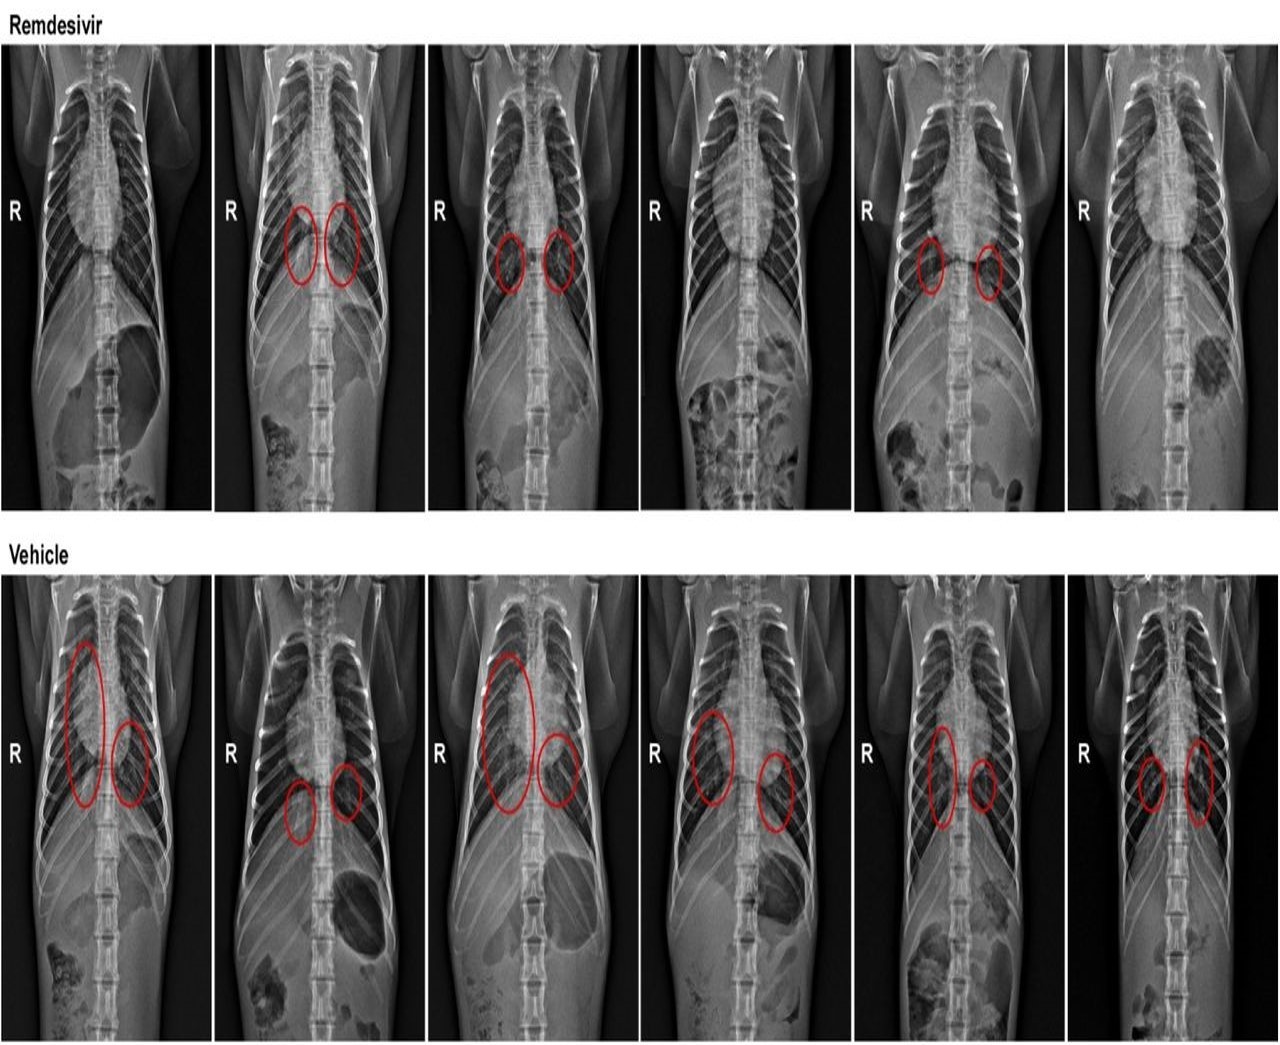

而從 X 光判斷肺部浸潤或病變,也發現用藥組的肺部病變較少。

兩組實驗動物的 X 光影像,紅圈處為肺部病變處,R 處為猴子的右側。

上圖為實驗組,下圖為對照組。圖/參考文獻3